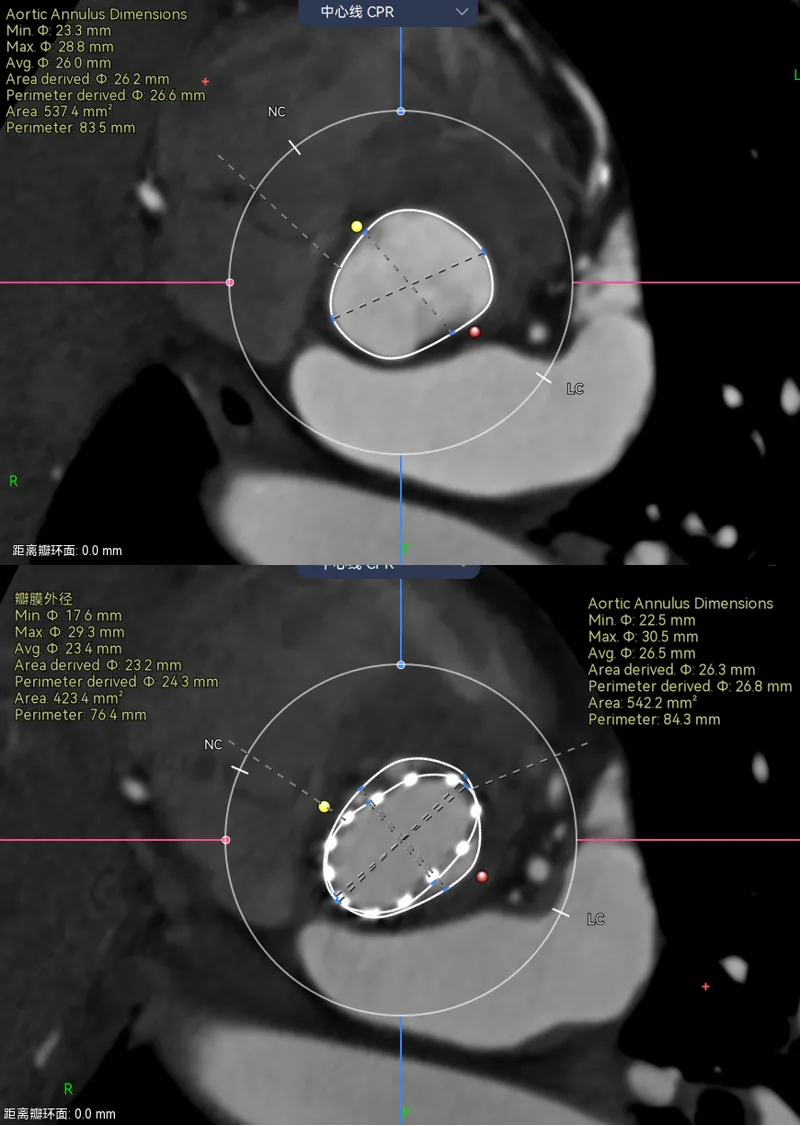

举个例子,病例-5,Type1的单边钙化,延伸到LVOT,瓣环这里笔者认为是因为把钙化避开的,因为他会对瓣膜有推挤作用。有些人则不会避开,这样瓣环会比预估的要大很多。

画法1-把钙化圈进去,瓣环径28。画法2-避开钙化,瓣环预估26.3,相差接近2mm。

那么这两种画法会对瓣膜型号选择造成很大的误判么?答案是不会,因为这个病人的限制在瓣上,你只能根据瓣上的空间来oversize,而且预估肯定会有点儿漏。